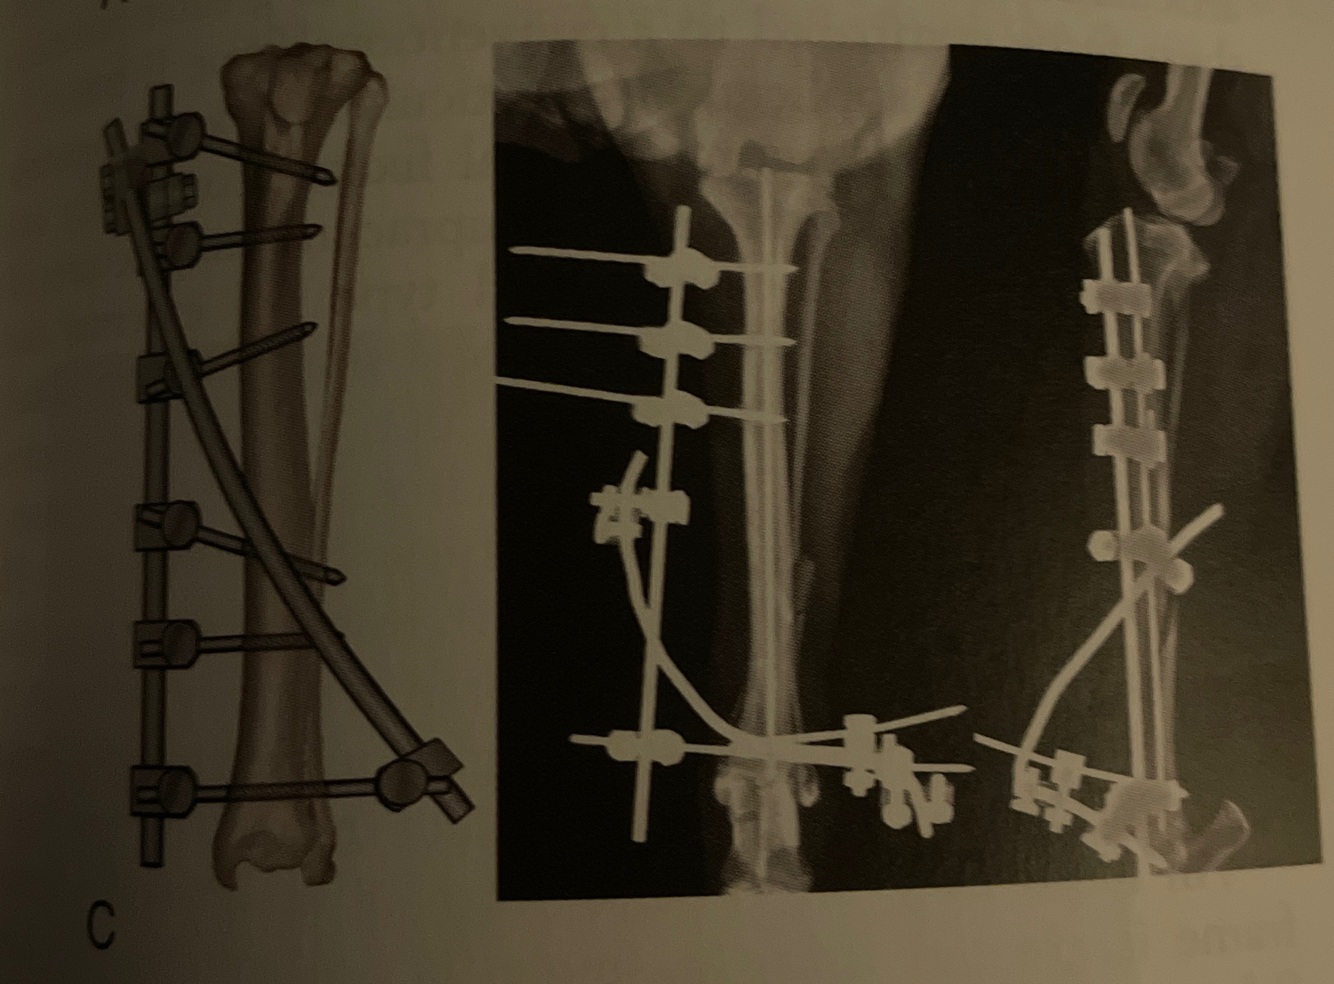

Type: I-II

Pins: Half and 1 full

Connecting Bars: 2

Pin Geometry:

-bilateral uniplanar